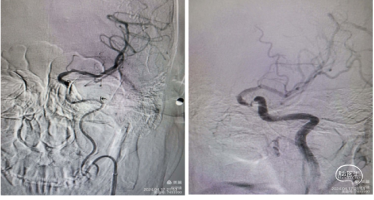

造影示:左侧颈内动脉起始部以远未向远端供血,左侧颈总动脉呈火苗样窜动。查询颈内动脉造影颈内动脉血流火苗样迟滞窜动。

8Fguiding到达C1段支撑070银蛇中间导管裸奔边上行边抽吸,抽出部分血栓,造影显示到血流达到C6段。

术中边推进导管边抽吸,抽出部分血栓,造影显示到血流达到C6段。

1、微导管到位:微导丝通过M1段艰涩困难,再次偿试通过M1段到达M2。携带微导管到达M2段,微导管造影显示远端有正向血流,在真腔内。下图1

2、支架释放:通过027微导管释放6X30mm 通桥蛟龙支架,静置5分钟后微造影,大脑中未显影,未见首过效应考虑血栓负荷较大。大脑前有血流。下图2